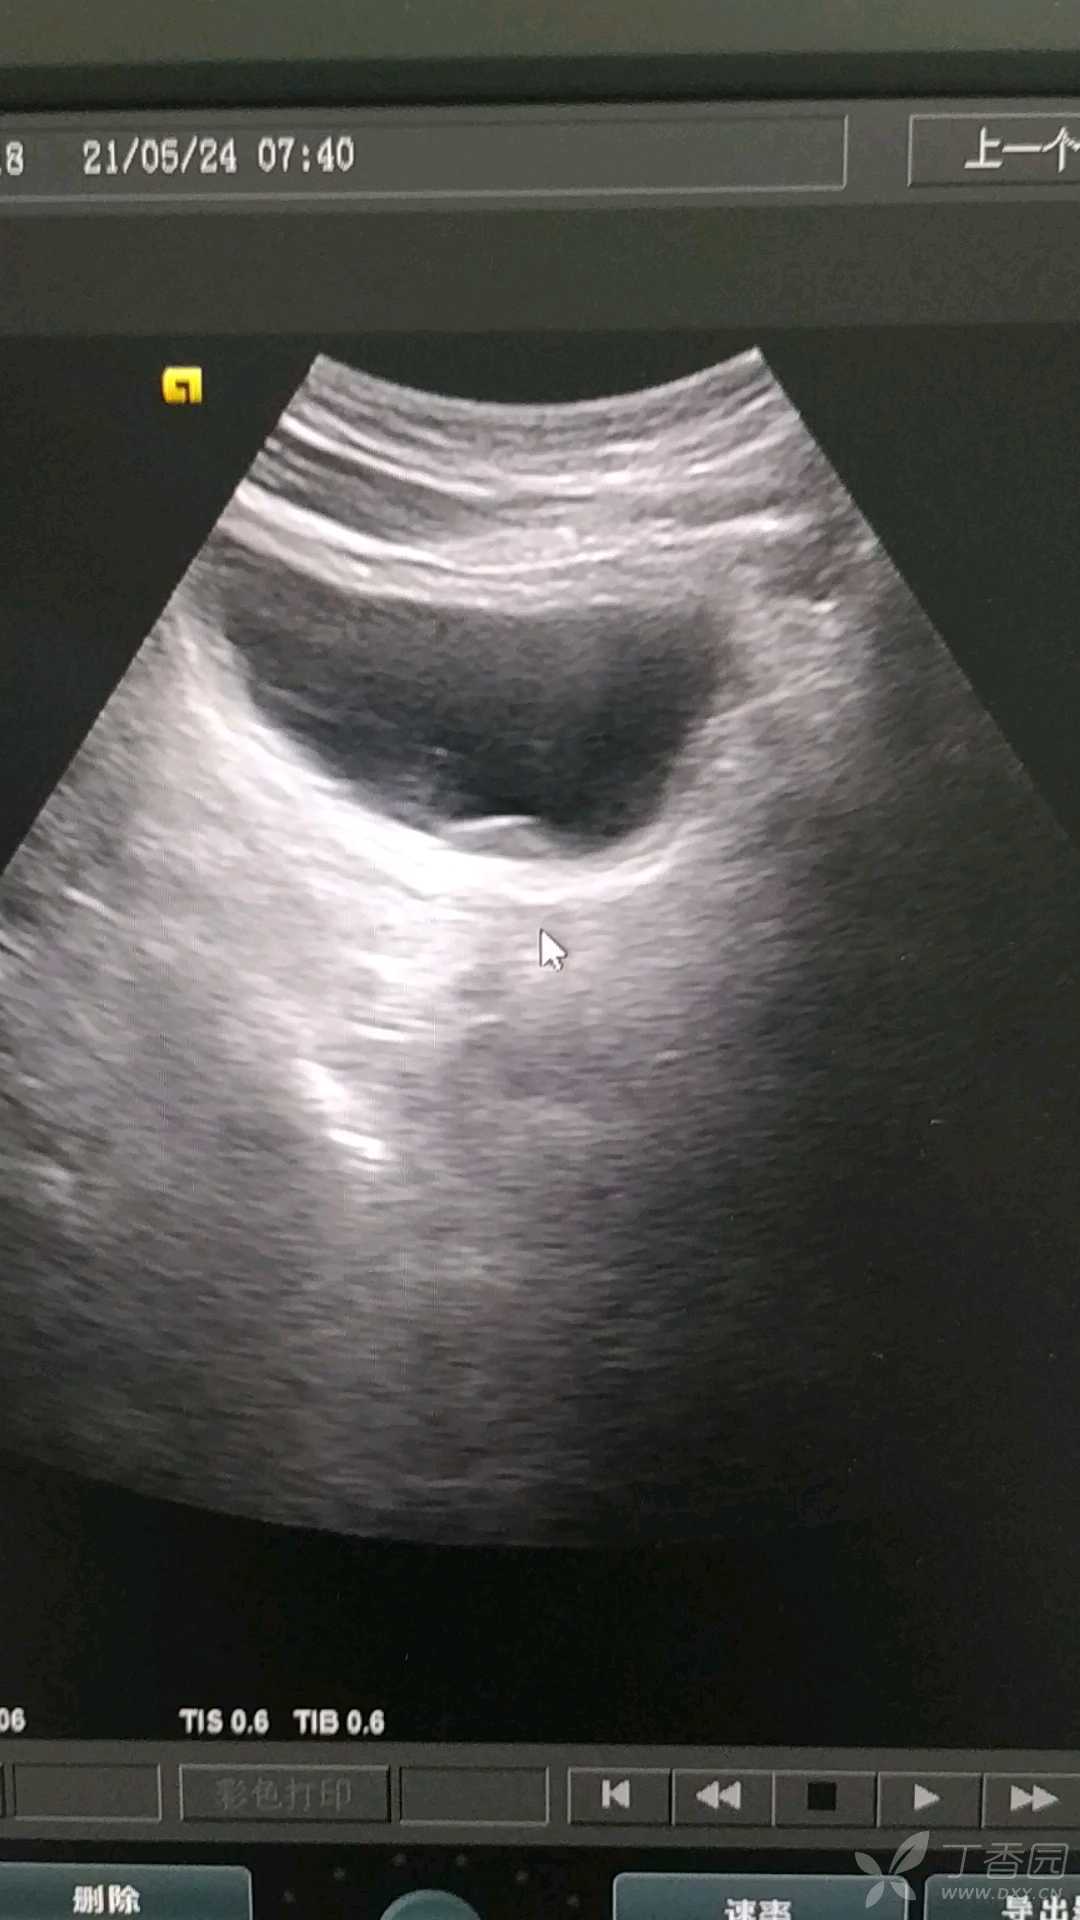

男,60岁,体检发现膀胱内可见形态不规则基底较宽的低回声团块,未见明显血流信号,无明显血尿史,考虑膀胱占位还是腺性膀胱炎?已建议做膀胱镜检查,等待病理回报。